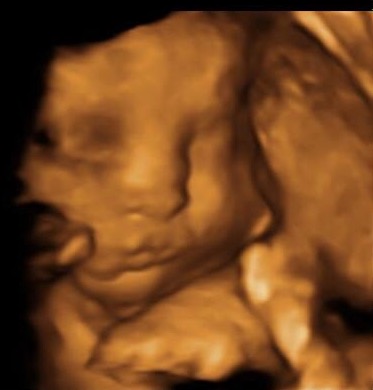

• Had ours at 28 weeks! This is the ONLY shot we got, but it was incredible! We enjoyed it.